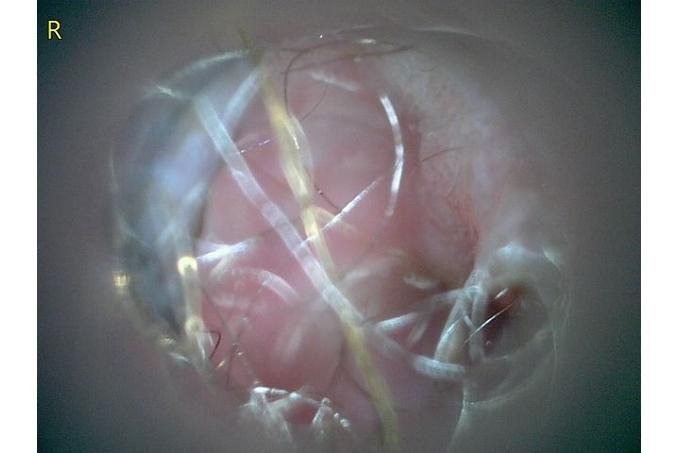

오늘 낮과 방금 5분전에 일어난 일인데요.. 강아지 귀질환 중에.. 옷입히고나서 귀를 바닥에 대고 비비거나, 귀에 통증을 호소하면서 잠깐 비틀비틀 걷는 경우 이런 경우 대체 뭘까요? 외이염일때도 이럴수도 있을까요? 아니면 중이염 내이염일지.. 한 2~3분정도 통증을 호소하다 지금은 또 정상이 됬는데 옷입을때만 옷의 목카라 부분이 귀에 닿을때 문제가 되는 느낌입니다. 평상시엔 가끔 양쪽 귀를 긁거나 귀를 자주 터는 정도입니다. 특이사항은 오른쪽귀 솜 돌돌 말아 귀안에 넣어줘도 비명을 지르며 엄청 아파하는데(작년11월경) 왼쪽은 안아파합니다)

mri ct 말고는 죽어도 중이염 내이염 또는 고막 확인이 불가능한가요?

제가 가장 알고싶은점은. 저렇게 옷깃에 귀가 시쳐도 아파할정도면 이게 외이염일까요 중이염일까요 내이염일까요? 얼마나 아픈지 옷한번 얇은 내복 평상시 입던거 입히면 입히고 나서 바로 온집을 돌아다니면서 바닥에 귀를 대고 정신나간애처럼 비비고 비틀비틀 걷습니다 그러다가 2~3분후 다시 정상으로 돌아옵니다

(근데 또 귀를 조물락 조물락 만져도 안아파합니다, 다만 솜을 길게 해서 넣으면 솜만 넣어도 아파합니다 특히 오른쪽요 왼쪽은 안아파합니다)